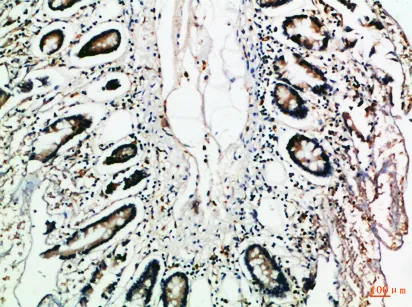

MCP-3 Rabbit Polyclonal Antibody

Cat: APRab13734